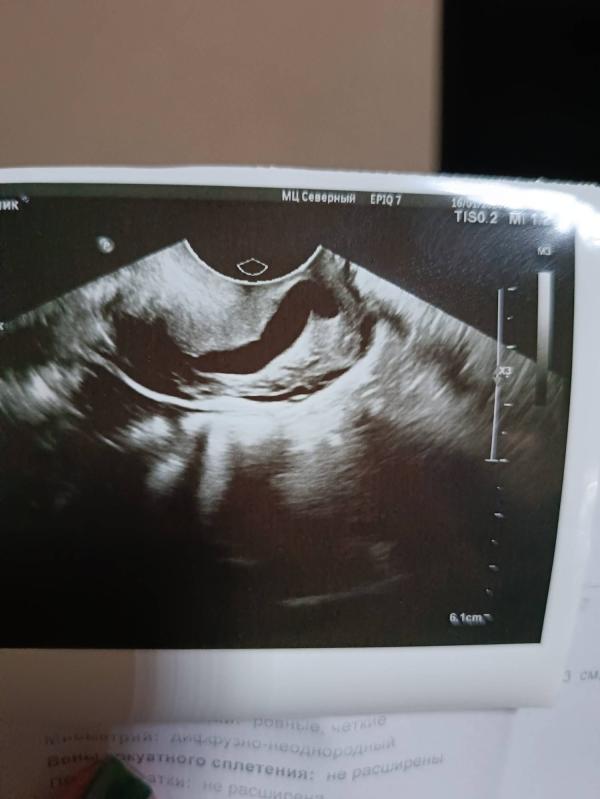

Всем добрый вечер, кто нибудь может сталкивался с таким, пока на узи не могут сказать что это, жду мрт, сделать получиться только в следующем месяце

Похож но рудраментальный рог

Жидкости там нет, полностью не функционирует, всё с меткой и трубами ок

А что в заключении написано? На гидросальпинкс ещё похоже